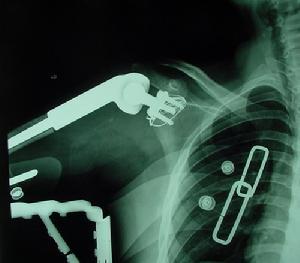

骨盆骨折是什么? 骨盆骨折是怎么回事?骨盆骨折是一种严重外伤多由直接暴力骨盆挤压所致多见于交通事故和塌方战时则为火器伤骨盆骨折创伤在半数以上伴有合并症或多发伤最严重的是创伤性失血性休克及盆腔脏器合并伤救治不当有很高的死亡率。